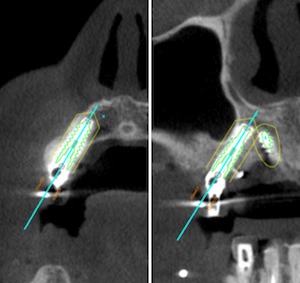

前歯部

前歯部は、歯根の一部を残しインプラントを埋入 /PET(Partial Extraction Therapy)する事で、骨のボリュームを確保することが可能となる。前歯部のインプラント治療で、審美を獲得する有効なテクニックの一つである。